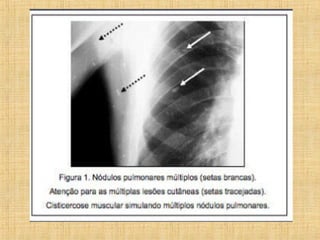

As principais informações do documento são: 1. Discute os padrões de doença pulmonar causados por metástases, incluindo nódulos, espessamento intersticial e obstrução das vias aéreas. 2. A prevalência de metástases pulmonares varia de 30-55% dependendo do tumor primário, e são mais comuns em pacientes acima de 50 anos. 3. Os achados clínicos mais comuns são dispneia, hemoptise e febre, enquanto exames de escarro ou lavado brô